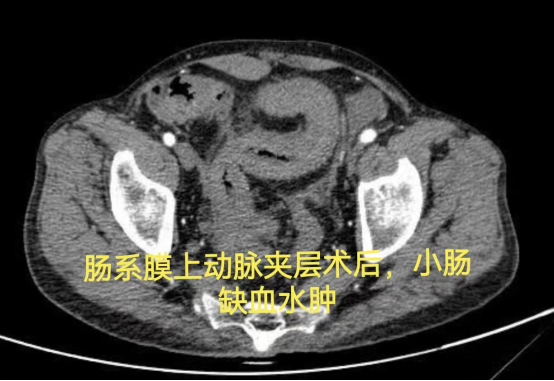

病情简述:53 岁男性,肠系膜上动脉夹层术后出现复杂肠瘘,经历三次手术仍无法愈合,入院时白蛋白仅 15.0 g/L(严重营养不良)。

诊疗破局: 面对再次手术的高风险,团队决定「先退一步」,将治疗重点转向营养支持。经过长达 3 个月的肠内联合静脉营养强化治疗,待患者身体状况改善后,再成功施行「腹腔镜肠粘连松解、瘘口小肠切除+远端回肠及回盲部结肠切除术」,最终成功康复。

技术体现: 有时候,充分的术前准备与对手术时机的精准把握,比手术本身更重要。